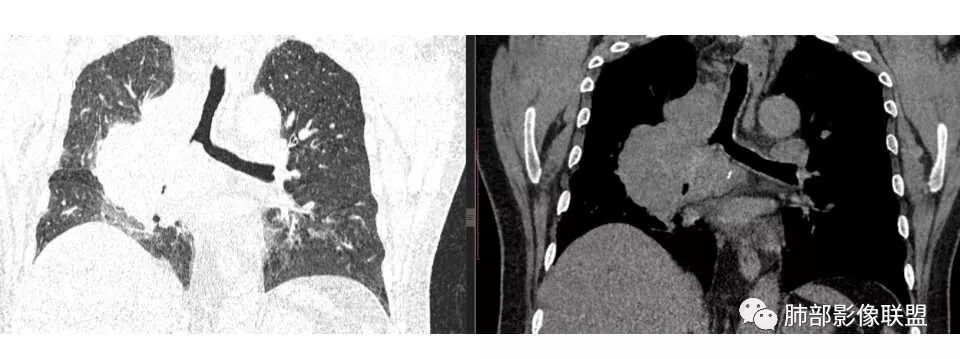

肺门及纵隔多发淋巴结。2L,4R,3区都有肿大淋巴结。

南边:有老师认为,血管前的这个应该是一个胸腺来源的。我觉得不是,为什么不符合胸腺来源呢,就看那个内乳动脉

双侧对比:右侧增粗,提示供血

但在内侧,不是外移

所以我倾向于淋巴结可能

胸腺瘤按理推压外移的多

而且胸腺癌转移不以淋巴结为主,如果淋巴结显著,按理周围侵袭性比较强,淋巴结也应该以附近为主,不应该以肺门为主,不符合引流规律。

支气管狭窄,壁有侵犯

局限性中央间质增厚,考虑癌性淋巴管炎

南边: 而且肺癌,一定受叶段的局限,这一例跨越右肺门,提示多个淋巴结融合

1.右肺上叶不规则结节影,右肺门及纵隔多结节并形成巨大块影,密度均匀,沿途支气管明显狭窄。

原发灶小或隐匿,肺门纵隔淋巴结异常增大,所谓“娘小崽大”常见于肺小细胞癌!

2.右肺小叶间隔增厚伴微小结节,提示癌性淋巴管炎。